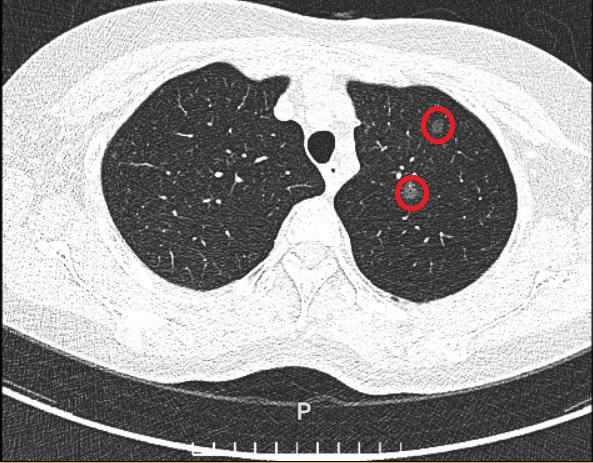

Bà Phương tiền sử hen phế quản điều trị bằng thuốc xịt, chụp CT liều thấp tại Bệnh viện Đa khoa Tâm Anh phát hiện hai nốt nhỏ ở thùy trên phổi trái. Một nốt kích thước 6,6×5,3 mm, mật độ thấp, đồng nhất, xếp loại Lung-RADS 2 (bảng phân loại nốt phổi nghi ngờ ung thư phổi). Nốt còn lại lớn, kích thước 11×5,9 mm, mật độ cao, không đồng nhất, bờ không đều, xếp hạng nguy cơ cao nhất (4X) theo LungRADS .

Hai nốt nhỏ ở thùy trên phối trái của bà Phương trên phim chụp CT liều thấp. Ảnh: Bệnh viện Đa khoa Tâm Anh